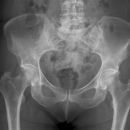

Becken a.p.

>90% aller Beckenringfrakturen lassen sich in der Übersichtsaufnahme, ggf. mit zusätzlicher Inlet und Outlet- Aufnahme (Bestimmung von Richtung und Ausmaß der Dislokation), diagnostizieren;

Beurteilungskriterien

- Symmetrie des Beckenskeletts, Position der Darmbeinkämme

- Weite und Symmetrie von Symphysenspalt (< 6mm) und ISF (< 4mm)

- Querfortsätze der unteren LWS, Kontur der Sakralforamina, ggf. CT

- Kontinuität der ilioischiadischen und iliopubischen Linie

- Azetabulumfraktur: vorderer und hinterer Pfannenrand, Pfannendachkontur, Köhlersche Tränenfigur, ggf. Zusatzaufnahmen (ap-Zielaufnahme, axiale, Ala- und Obturatoraufnahme), sowie CT

- Schenkelhalswinkel, Weite des Hüftgelenksspalt (4-5mm nach medial, 3-4mm nach kranial)

- Hüftluxation? Hüftkopf in der Beckenübersicht und in der axialen Aufnahme in der Pfanne zentriert?